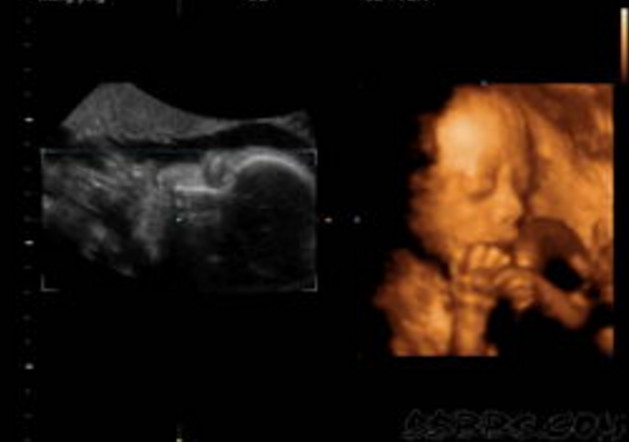

胎儿得了唇腭裂,受不受怙恃的遗传呢?

实在,唇腭裂是由多种要素惹起的疾病,而遗传的确是其中的一个主要缘由。假如直系亲属有唇裂者,其后世发作该病的比率为4%摆布。别的,母亲在孕期打仗放射线、已经服用药物、头三个月内传染病毒性疾病或其他疾病,如伤风、风疹等,怀胎早期营养不良等,都能够招致胎儿呈现唇腭裂。